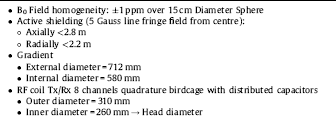

The MR scanner is designed to be fully compatible with the PET module. The magnet integrates a new technology bringing together a very compact design with a cryogen-free magnet at the most widely available clinical field of 1.5T. The limited axial dimension reduces the claustrophobic effects for the patient and gives the possibility of PET bolus injection under control, the arms outside of the magnet. Fig. 4 represents the actual dimension of the magnet produced by SSI, Superconducting Systems Inc., U.S.A. The magnet coil is cooled with a cryocooler that takes a minimum amount of space near the magnet and allows the system to work without any cryogenic fluids (no liquid helium, no liquid nitrogen). Eighteen days are needed to cool down the magnet before energizing it. As a result, the simpler safety requirements reduce the cost and the installation complexity.

Fig. 4 Schematic drawing of the MR magnet.

The magnet has been temporarily installed at RS2D (Strasbourg, France) for testing. A dedicated Faraday cage was built and installed around it. A description of the general properties of the MR component for the parts in the operating room and in the technical room is given in Table 2.

Table 2 MR System components.

In addition to the measurement of the static B0 and of the magnetic field gradient strengths, imaging measurements were carried out on a standard MR phantom consisting of a PMMA cube (135 × 135 × 135 mm3) inside a cylinder (200 mm diameter and 160 mm length) filled with a preparation composed of 5 l of demineralized water, 18 g of NaCl and 6.25 g of CuSO4.

The selected RF coil is designed in two layers: the outer layer is a dedicated transmit-only, quadrature birdcage coil and the inner part is a receive-only, 8-channel phased array coil. Since the delivery date for this coil is December 2017, two other coils were used for testing the sequences to be implemented on the MR Scanner. The second one is an eight-channel degenerate birdcage coil for transmission and detection, manufactured using non-magnetic, fixed and variable capacitors located outside the PET field-of-view. The coils support frame is 3D printed on a polycarbonate substrate. The third coil is a quadrature birdcage coil built with copper tape on a PMMA cylinder tuned for the 1.5 T magnet.